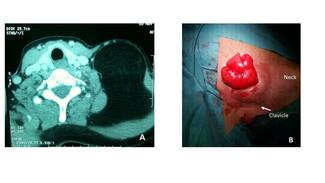

El Hassane Kabiri, MD, PhD; Massine El Hammoumi, MD; Mohamed Bhairis, MD

This Case Q&A discusses giant lipomas, including the clinical presentation and potential etiologies, appropriate imaging procedures, differential diagnoses, and surgical approaches to treatment.